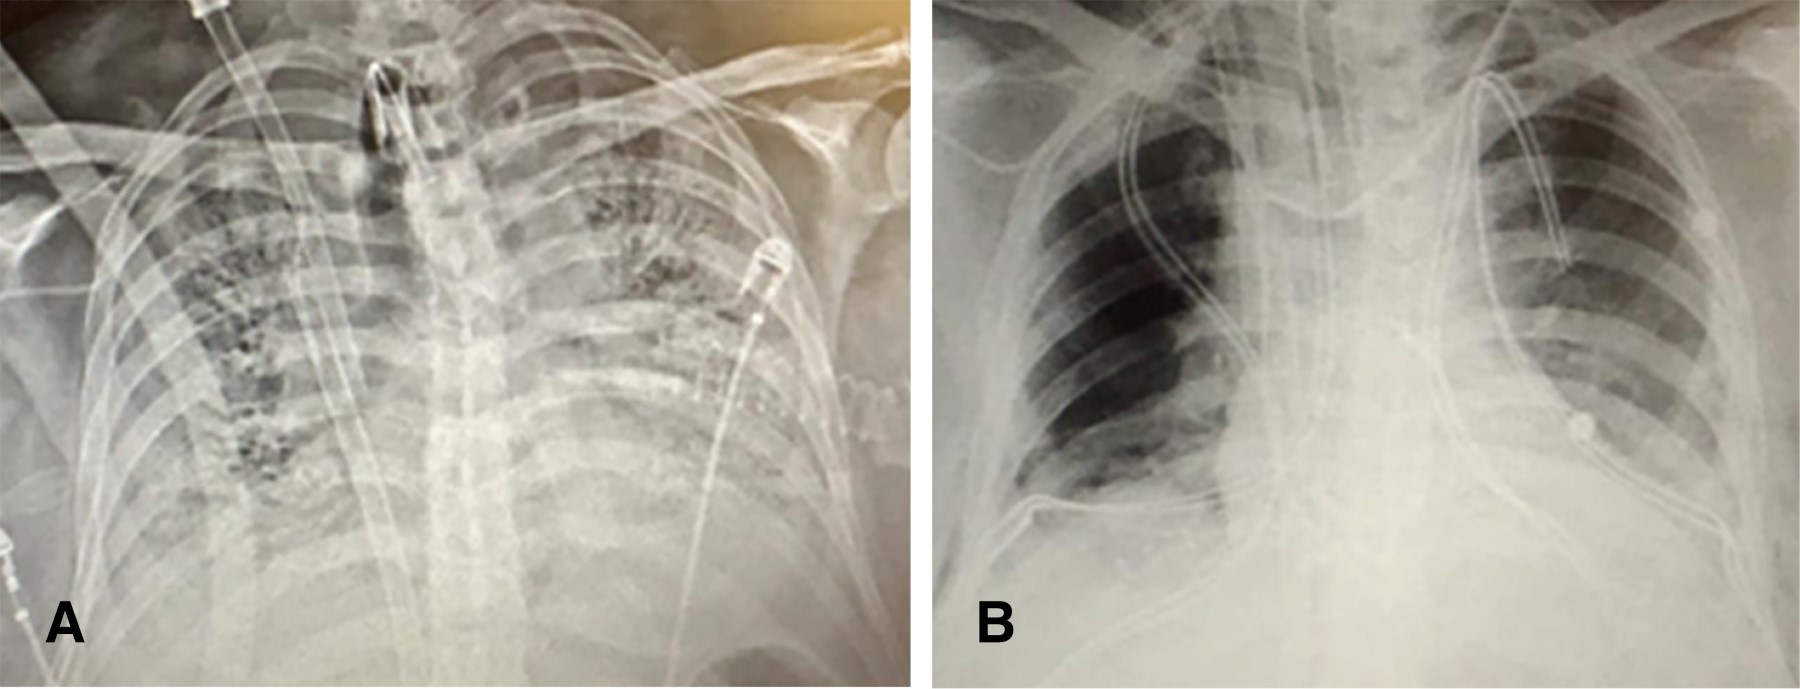

Figure 1